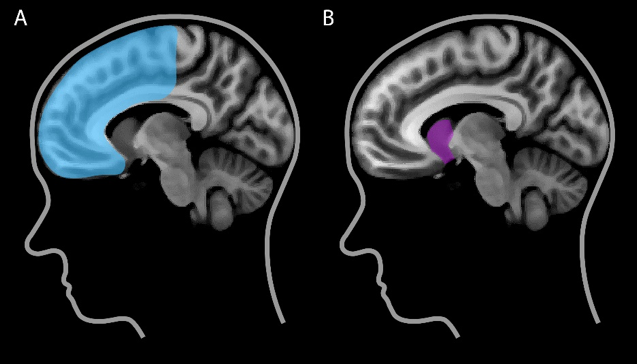

Twee gebieden in onze hersenen lijken cruciaal voor

feedback leren: het

striatum en de

frontale cortex (Maia, 2009). Het

striatum ligt diep in de hersenen (Figuur 1a) en signaleert in hoeverre de daadwerkelijke gevolgen van een keuze prettiger of minder prettig uitvallen dan je van tevoren verwachtte. De

frontale cortex bevindt zich aan de voorkant van de hersenen achter het voorhoofd (Figuur 1b) en is betrokken bij doelgericht gedrag: het maken van (een reeks) keuzes met een bepaald doel voor ogen. Succesvolle keuzes kunnen echter alleen worden gemaakt als de betrokken hersengebieden goed met elkaar communiceren. Dat hangt onder andere af van hoe goed deze gebieden fysiek met elkaar verbonden zijn (Kanai en Rees, 2011). Vergelijk het met de snelweg tussen Amsterdam en Utrecht: hoe breder de weg, hoe meer auto’s er per uur overheen kunnen.